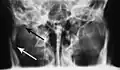

lateral oblique image demonstrating a fractured mandible.